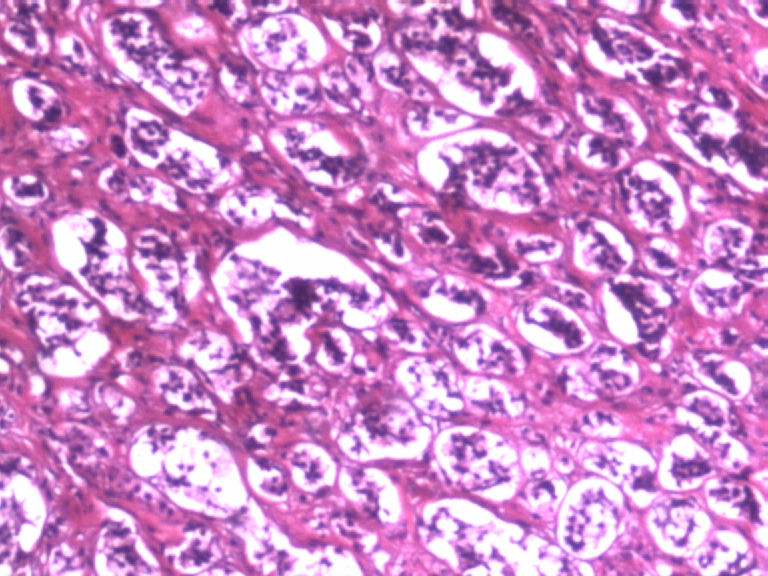

男,50岁,阑尾长7厘米,直径0.4---0.6厘米。剖开:尖端看见淡黄色区,不规则,界限欠清,0.15*0.2厘米,质中。

×参考诊断

考虑阑尾类癌

像类癌,有些粘液,标记一下Syn、CgA,有可能是杯状细胞类癌

按照胃肠胰腺神经内分泌肿瘤WHO2010分类,该例应属于NET G1(神经内分泌瘤,1级)。需标记Syn, CgA, Ki67.

倾向神经内分泌肿瘤,建议做CgA、SYN、Ki-67检查。

阑尾的神经内分泌肿瘤我们已经碰到好几例了,一般都在阑尾尖端,取材一定要规范,这样可以减少漏诊率。